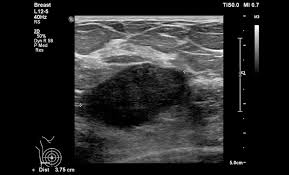

What Does Breast Cancer Look Like Pictures - Woman Shares Photo Of Her Breast To Show What Cancer Symptoms Look Like The Independent The Independent / The american cancer society couldn't do what we do without the support of our partners.. Brest) cancer is a common cancer among women. Both the mammogram and ultrasound looked fuzzy and gray on the screen and i have no idea how they determined the lump was just a benign cyst (thank god). People who are over 40. There's been a lot of press about not needing to do self breast exams, but i really do think it's important to have self awareness about how things might change in the appearance of your. One of the most common malignancies in women in the us cancer that starts in the breast.

Pictures and description of what does breast cancer look like on mammogram for 5 categories. Brest) cancer is a common cancer among women. One type of breast cancer, inflammatory breast cancer, does not usually cause a lump but instead in contrast to breast cancer tumors, benign lumps are often squishy or feel like a soft rubber ball with when looking at mammogram pictures, cancers often appear bright and the area around the. If the diagnosis is delayed, the cancer can spread to distant sites. Instead, breast skin can become thick, red, and look pitted, like an orange peel.

Without having seen a picture randomly with real information, i wouldn't have known what to look for, erin posted. Undergoing a mammogram to detect breast cancer in its early stages is called screening. Ibc doesn't look like a typical breast cancer. What is invasive breast cancer versus noninvasive breast cancer? It often does not cause a breast lump, and it might not show up on a mammogram. Sometimes, these spots have a raised border with an indentation in the center, according. Breast cancer lumps are usually hard and irregularly shaped. The 15 worst things you can say to someone with breast cancer. This is one of the many reasons it's important to know what is normal for your body. But remember, if breast cancer is caught while still 'in situ' (not yet penetrating the breast duct walls) there is very little risk of anything really bad happening. Not feel, but look like. I was diagnosed with breast cancer 5 days later and with stage 4 the following month. If the diagnosis is delayed, the cancer can spread to distant sites.